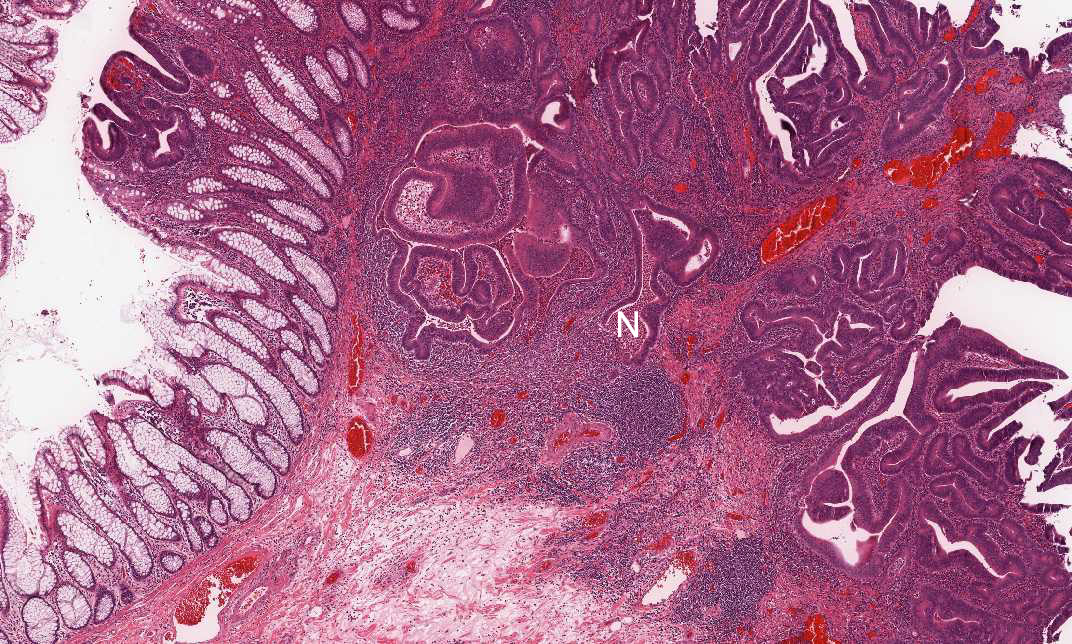

Area 3: This image is taken at the edge of the tumor where you can see the the relationship between the normal area (N), muscularis mucosa (arrow) and the invading tumor (In).

Hematoxylin & eosin